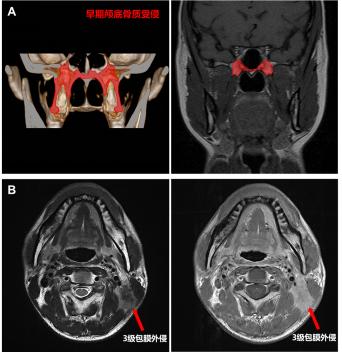

隨著核磁共振技術(shù)的發(fā)展,鼻咽癌早期顱底骨質(zhì)受侵(僅翼突或蝶骨基底受侵)患者的檢出率顯著提高,占到所有患者的10-20%,原發(fā)灶分期為T3患者的20-30%。既往研究報道早期顱底骨質(zhì)受侵患者預(yù)后較好,或可豁免高強度的化療。本次研究結(jié)果顯示,早期顱底骨質(zhì)受侵的T3患者的5年生存率為91.9%,顯著優(yōu)于其余T3患者(88.8%),且與T2患者相似(91.5%)。因此,建議將輕度顱底骨質(zhì)受侵降為T2。

頸部嚴重淋巴結(jié)包膜外侵(即3級包膜外侵,腫瘤突破淋巴結(jié)包膜侵犯淋巴結(jié)周圍鄰近結(jié)構(gòu))患者往往臨床預(yù)后較差,治療后極易發(fā)生復(fù)發(fā)轉(zhuǎn)移。研究發(fā)現(xiàn)原淋巴結(jié)分期為N1和N2患者中嚴重頸部淋巴結(jié)包膜外侵患者5年生存率分別為82.0%和77.1%,與N3的78.7%接近。因此,建議嚴重頸部淋巴結(jié)包膜外侵升級為N3。

A早期顱底骨質(zhì)受侵:僅有翼突或蝶骨基底的顱底骨質(zhì)受侵

B 3級淋巴結(jié)包膜外侵:腫瘤突破淋巴結(jié)包膜侵犯淋巴結(jié)周圍鄰近結(jié)構(gòu)